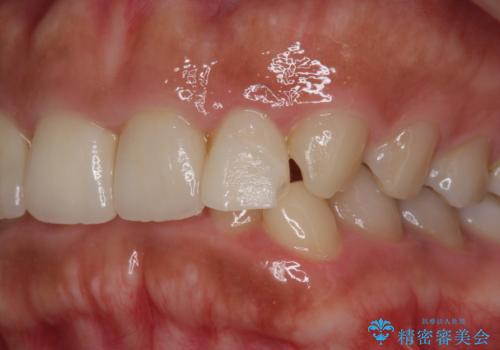

欠けた前歯を綺麗にしたい

- 「欠けてしまった前歯のコンポジットレジン修復をくり返していたが、すぐ外れてしまい困っている。」

、と前歯の欠けの改善を求めて来院されました。

噛み合わせが深く、前歯の突き上げが大きいため欠けの繰り返しを防ぐべくセラミッククラウンによる補綴を行うこととしました。

審美性の改善を達成することができました。